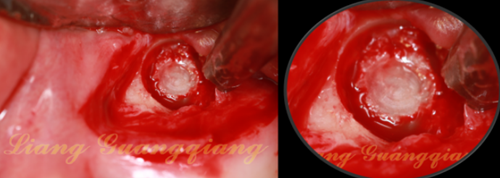

一次性注射器,連接50ml注射器上的針頭,輕輕刺入囊腫外側(cè)壁,緩慢吸出里面的液體。

膜收腰的狹窄區(qū)剛好卡在洞口,大部分的膜被平攤在上頜竇膜下方:1,防止殘余的囊液污染骨粉。2.防止大顆粒的骨粉刺傷上頜竇膜。下方植入骨粉。

骨粉要塞實,外面的生物膜正好折下來蓋住窗口